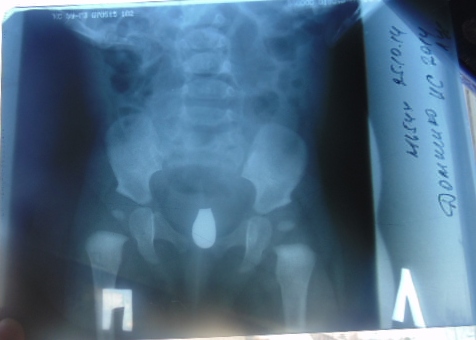

Здравствуйте, Моей дочке 3,5 мес. Наш хирург подозревает недоразвитие тб суставов отправил на узи. Результаты: визуализация не удовлетворительная, форма головки кости округлая, точки окостенения нет, лимбус треугольный, костный выступ прямоугольный правый и левый угол альфа 60 бетта 55. Тип 1а. Его результаты не устроили отправил на ренген. На ренгене указали углы справа 26, слева 25 градусов. Что это значит. Дисплазия это или может быть тонус и что делать? Зарядку делаем ежедневно.

Здравствуйте! Нам сейчас 5 месяцев, в два поставили диагноз, дисплазия тазобедренного сустава назначили лечение: подушка Фрейка 1 месяц, десять сеансов массажа и электрофорез, явка в 4 месяца. Мы уезжали на два месяца в другой регион там по месту прибытия встали на учет. После осмотра ребенка и снимка врач отменил подушку фрейка, сказал, что массажа и электрофореза будет достаточно. Подушку Фрейка мы не носили. По возвращению домой пошли на отметку к нашему ортопеду, нас отправили делать снимок по результатам снимка правый угол 24 градуса, левый угол 30 градусов. Диагноз: Дисплазия т/б сустава (дисплазия вертлужной впадины). Назначила: массаж общий№10, гимнастика, электрофорез, витамин D,подушка фрейка 2 месяца. Мы в растерянности! Подскажите пожалуйста адекватное ли лечение нам назначили? Я читала, что перинку Фрейка назначают до 4-5 месяцев. Заранее спасибо. Извиняюсь за качество снимка, снимок делала через окно.